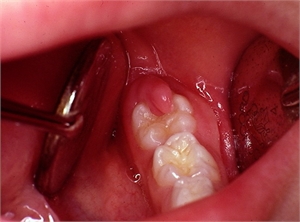

Operculectomy is a surgical removal of the inflamed flap of soft tissues surrounding a partially erupted tooth. This soft tissue is widely known as the operculum. A successful operculectomy surgery leaves an area that is easy to clean as the tooth erupts. A partially erupted tooth is usually more prone to decay and gum disease which causes inflammation of the gums and adjacent tooth tissues resulting into discomfort and pain. The operculectomy is done with a surgical scalpel, an electrocautery device or with dental surgical lasers. The operculum accumulates food debris and harbors bacteria which is detrimental to the oral hygiene.

3. Operculectomy. The incision of the soft tissue flap reduces the pocket around the tooth, and the area of debris retention. The dentist achieves a self cleansing surface and the patient saliva mechanically washes out any food particles in this area. Operculectomy can be done with a conventional scalpel, electrocauter or laser. It is good practice to combine operculectomy with a course of antibiotics or root scaling. Operculectomy procedure is carried out under local anaesthetic and it is painless. However, the patient may have post operative sensitivity for up to three days after the operation.